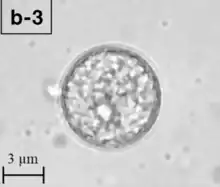

| A Balamuthia mandrillaris cyst | |

B. mandrillaris is a free-living, heterotrophic amoeba, consisting of a standard complement of organelles surrounded by a three-layered cell wall (thought to be made of cellulose), and with an abnormally large cell nucleus. On average, a Balamuthia trophozoite is about 30 to 120 μm in diameter. The cysts fall around this range, as well.[8]

Balamuthia's lifecycle, like the Acanthamoeba, consists of a cystic stage and a non-flagellated trophozoite stage, both of which are infectious, and both of which can be identified in the brain tissue on microscopic examination of brain biopsies performed on infected individuals. The trophozoite is pleomorphic and uninucleated, but binucleated forms are occasionally seen. Cysts are also uninucleated, possessing three walls: an outer thin irregular ectocyst, an inner thick endocyst, and a middle amorphous fibrillar mesocyst.[9]